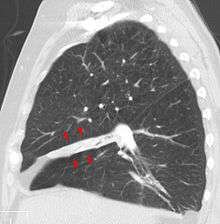

Atelectasis of a person's right lung | |

Atelectasis is the collapse or closure of a lung resulting in reduced or absent gas exchange. It may affect part or all of a lung.[1] It is usually not bilateral. It is a condition where the alveoli are deflated down to little or no volume, as distinct from pulmonary consolidation, in which they are filled with liquid. It is often called a collapsed lung, although that term may also refer to pneumothorax.[2]